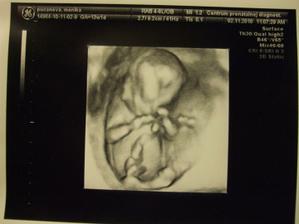

Naše čakanie sa vyplatilo 🙂))